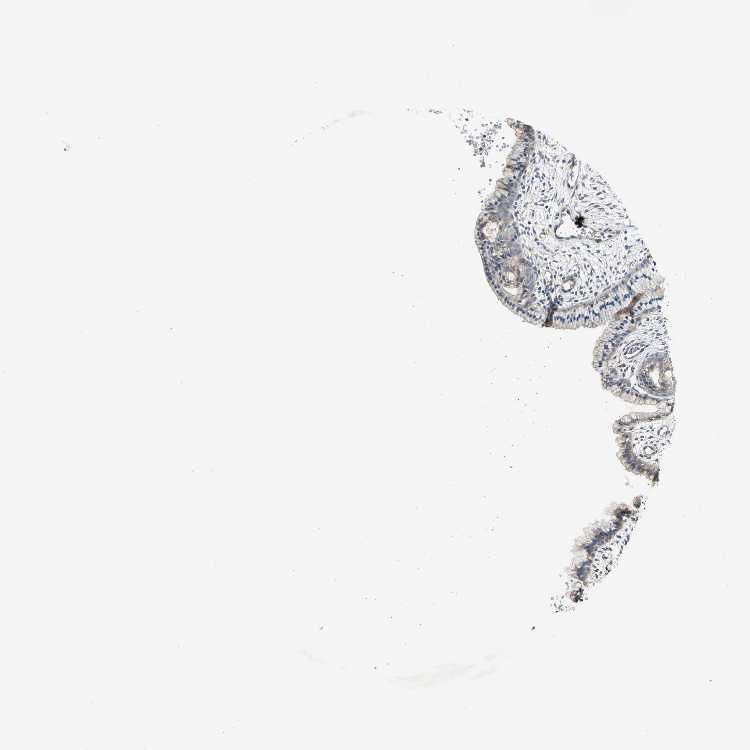

CERVIX - Antibody stainingi

Antibody staining in the annotated cell types in the current human tissue is reported as not detected, low, medium, or high, based on conventional immunohistochemistry profiling in selected tissues. This score is based on the combination of the staining intensity and fraction of stained cells.

Each image is clickable and will lead to virtual microscopy that enables deeper exploration of all samples and also displays staining intensity scores, fraction scores and subcellular localization as well as patient and tissue information for each sample.

Antibody HPA004895Antibody CAB013018

Glandular cells LowMedium

Squamous epithelial cells -Medium